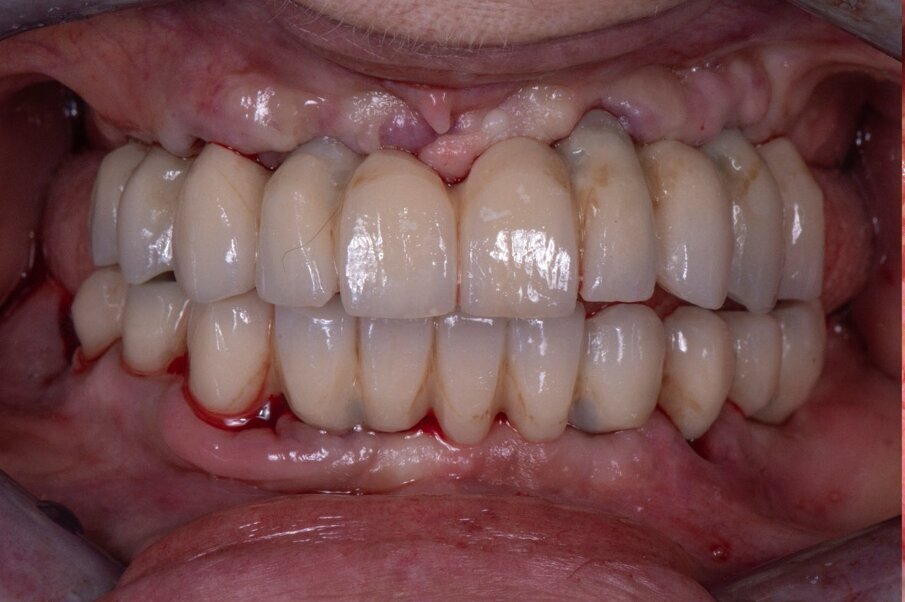

Paziente donna di ottant’anni, presenta uno stato di salute ottimale, non assume farmaci. Dal punto di vista odontoiatrico chiede una riabilitazione delle due arcate con dei denti fissi perché le attuali protesi removibili con ganci le stanno creando ormai da troppi anni un grande disagio. Come dalla ortopantomografia possiamo evidenziare uno stato ormai precario degli elementi rimasti (Figg. 1-3).

Fig. 2_OPT caso iniziale.